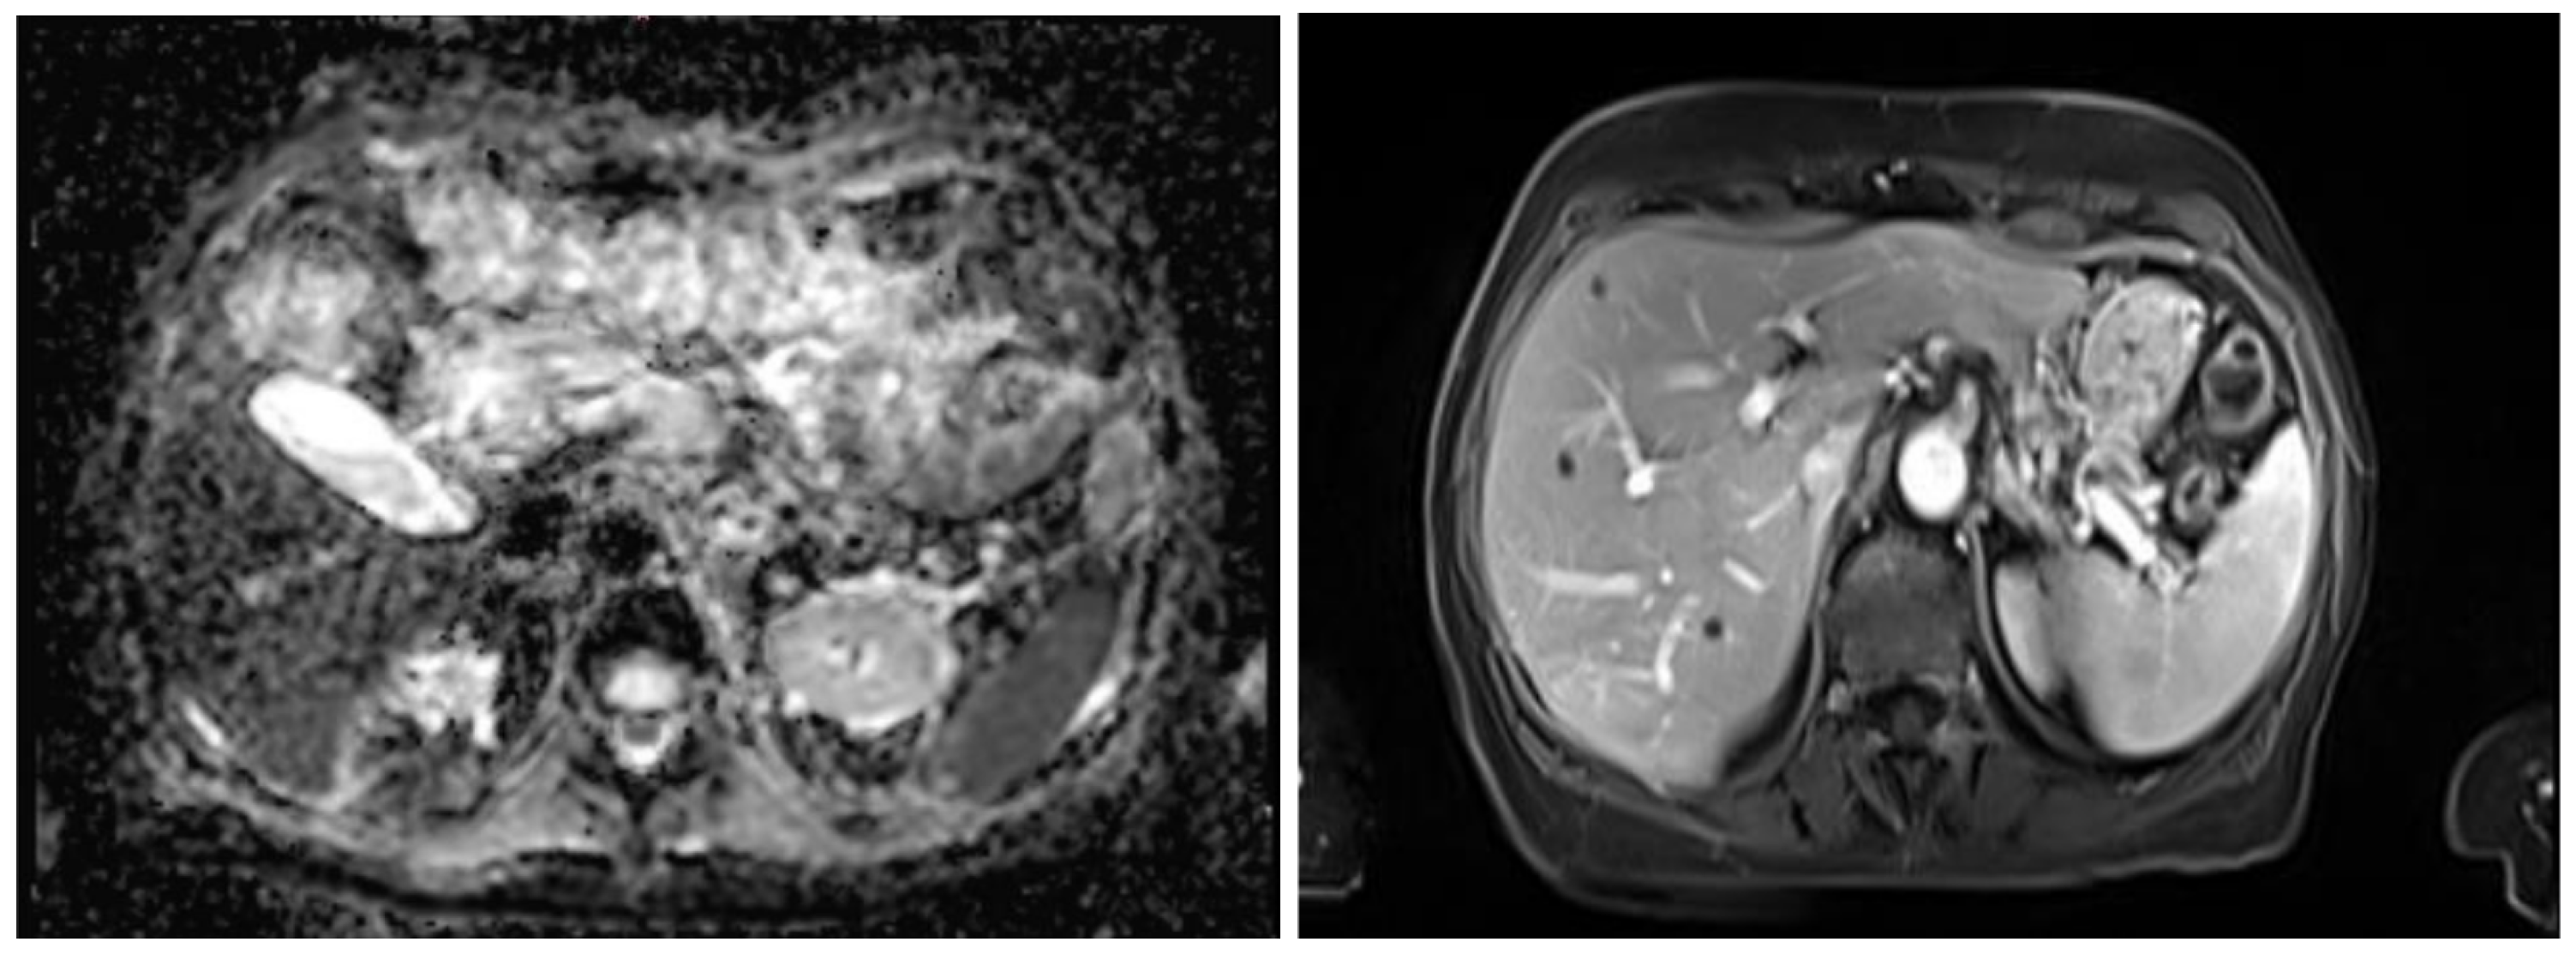

This section describes the dataset, model architecture, and training procedures used for MRI sequence classification (T1 vs. T2) and anatomical segmentation as part of an AI pipeline for surgical planning. In the stage of classification, the study was conducted in three stages of training, progressively refining the dataset and model configuration. The dataset was refined across three training stages: an initial set of 363 volumes, a filtered and expanded set of 2286 volumes, and a third training stage focusing on extended epochs to optimize performance. A ResNet18 architecture was adapted for volumetric inputs and binary classification. To support this task, the inherent contrast differences between T1- and T2-weighted MRI were leveraged: in T1-weighted images, fat-rich tissues appear hyperintense, providing clear anatomical boundary definition, whereas in T2-weighted images the fluid-rich structures such as cerebrospinal fluid appear hyperintense, enhancing contrast in edema, inflammation, and other fluid-related pathologies, as shown in Figure 1. In contrast, fluid-containing structures present higher signal intensity, making them more suitable for highlighting pathological or inflammatory conditions. Next, a segmentation stage was implemented, which employed a modular nnU-Net framework with networks specialized in anatomical subsets including major organs, vasculature, musculoskeletal structures, and tumors. Training used the Adam optimizer with carefully selected batch sizes, learning rates, and epochs adjusted per dataset and task. Model performance was evaluated using Dice coefficient, Intersection over Union, and Hausdorff distance. The subsequent subsections present a comprehensive and detailed explanation.

Figure 1. The (left) picture shows a T1-weighted MRI scan, where fat-rich tissues appear hyperintense, providing clear anatomical boundary definition. The (right) picture shows T2-weighted MRI scan, where fluid-rich structures such as cerebrospinal fluid appear hyperintense, enhancing contrast in edema, inflammation, and other fluid-related pathologies.